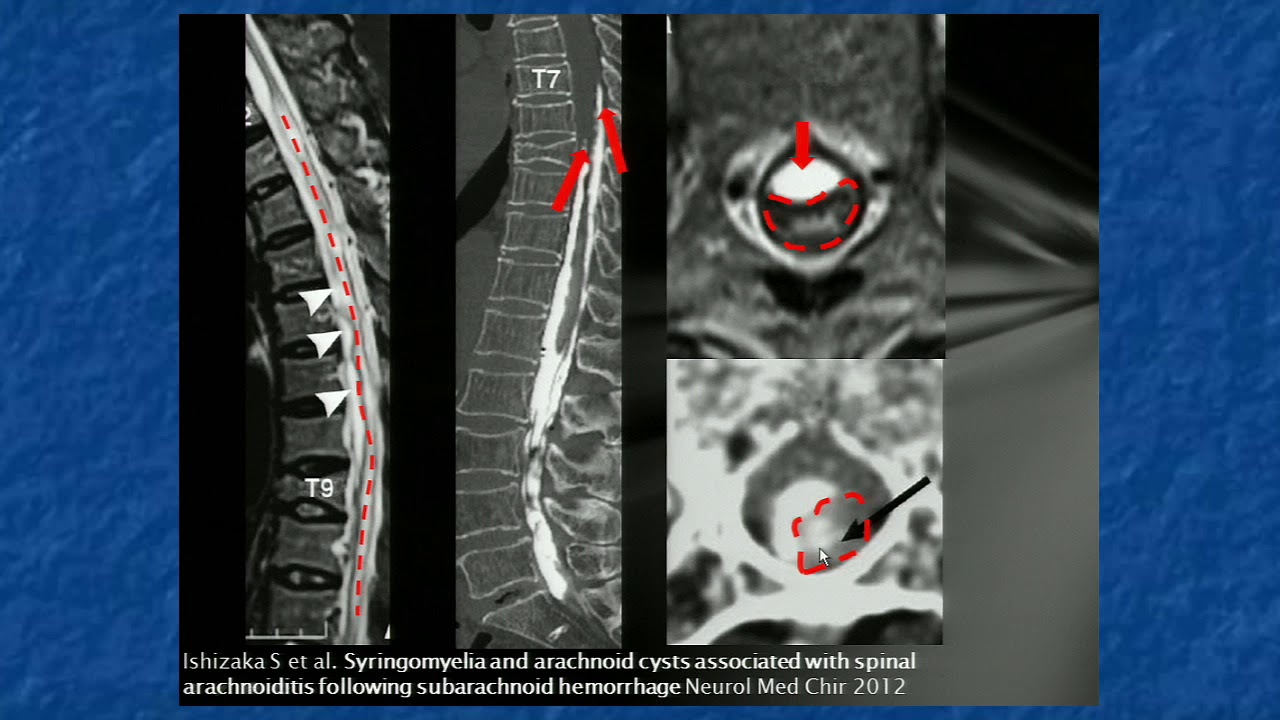

Vediamo 09 Patologie infiammatorie del midollo spinale. Alessandro Stecco di tendenza